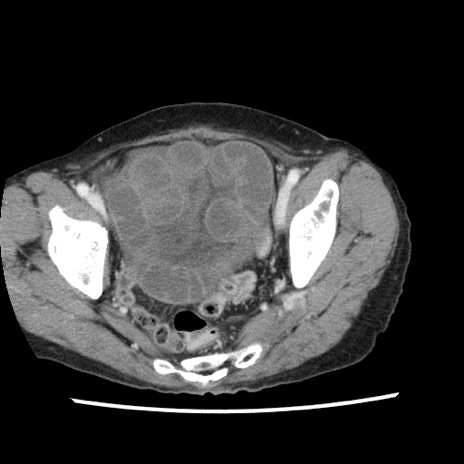

矢状断像

【症例】80歳代女性

【主訴】腹痛

【現病歴】8時間前から腹痛あり来院。

【既往歴】糖尿病、脂質異常症、子宮体癌にて子宮全摘術

【身体所見】意識清明・会話良好だが腹痛で苦悶様、全腹部にわたって反跳痛と圧痛あり

【データ】WBC 13600、CRP 0.14、LDH 224、CK 90